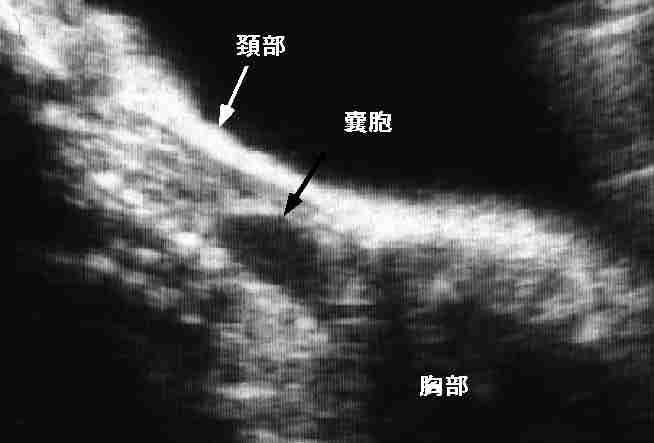

Esophageal atresia: Cystic lesion is usually identified in the upper mediastinum.